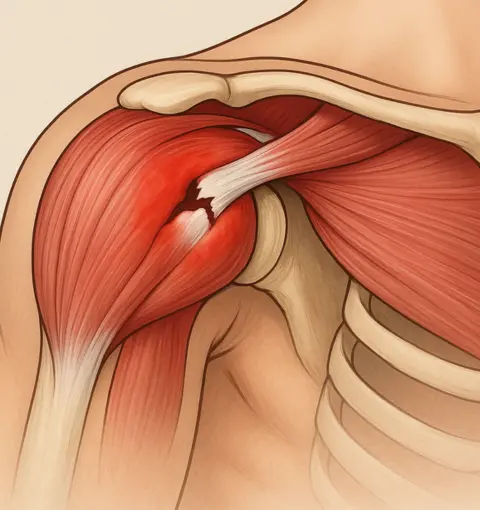

Lesão no Manguito Rotador

O manguito rotador é um conjunto de músculos e tendões essenciais para o movimento do ombro. Oferecemos tratamento especializado para lesões e rupturas.

O ortopedista especialista em ombro em Goiânia trata diversas condições como tendinite, bursite, lesões do manguito rotador, luxação do ombro, rompimento de tendões, artrose, capsulite adesiva (ombro congelado), fraturas e outras patologias que afetam a articulação do ombro.